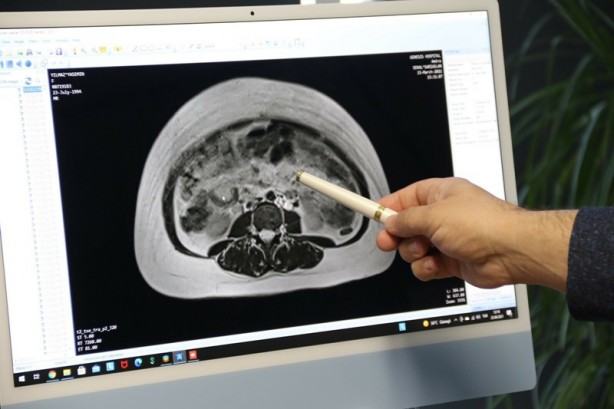

Dış merkezde çekilen MR görüntülerine de baktığımızda karın içini kaplayan 25 santimetrelik bir kistik lezyon gördük. Kist büyümüş ve iltihaplanarak yüksek ihtimalle içine kanama yapmış. Sonuç olarak da enfeksiyon oluşturmuş. Buna bağlı tüm karnı dolduran 25 santimetrelik iltihaplı bir kist vardı. Antibiyotikler verdikten sonra süre dolunca hastayı ameliyata aldık. Ameliyatı laparoskopik olarak gerçekleştirdik. Kistin içinden ortalama 2 buçuk litre iltihap boşalttık. Bu iltihabı boşalttıktan sonra kist ancak müdahale edilebilir hale geldi ve çıkarttık. İçerdeki enfeksiyonu kuruttuktan sonra hastamızı taburcu ettik. Şu anda gayet iyi hiçbir sorunu yok ve kontrollerde de geriye hiçbir şey kalmamış” şeklinde konuştu.